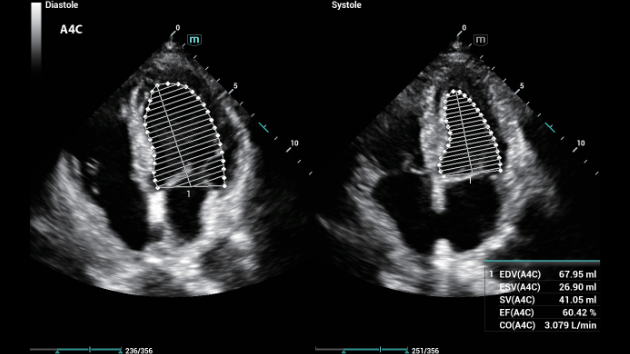

Indipendentemente dalle attività svolte in ospedale o in clinica, oppure se si desidera affinare le proprie capacità nella diagnostica per immagini generale negli ambiti della salute della donna o cardiovascolare, questa serie di soluzioni fornirà potenti strumenti per essere sempre un passo avanti.

Soluzioni di diagnostica per immagini complete con tecnologia ZST+

La piattaforma ZST+ è un'innovazione straordinaria, che rappresenta un'evoluzione nel campo dell'ecografia. Grazie alla trasformazione delle metriche a ultrasuoni dal beamforming convenzionale all'elaborazione basata sui dati di canale, supera la tradizionale limitazione del trade-off tra risoluzione spaziale, risoluzione temporale e uniformità dei tessuti, offrendo una qualità d'immagine eccezionale per infinite soluzioni di imaging con miglioramenti continui.